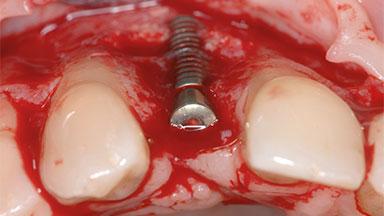

A 35-year old female patient was referred to the Department of Oral Surgery and Stomatology at the University of Bern, Switzerland, for examination of an implant site that had exhibited clinical signs of slightly delayed wound healing. In addition, the referring clinician found no evidence for a facial bone wall when she raised a flap to gain access to the implant for abutment connection. Four months earlier, she had inserted a bone-level implant in a single-tooth gap, where the lateral incisor had been extracted due to a chronic periapical lesion on the mesial aspect of the root. Implant placement was combined with simultaneous bone augmentation using deproteinized bovine bone mineral (DBBM, Bio-Oss®; Geistlich, Wolhusen, Switzerland) and a collagen membrane (Bio- Gide®; Geistlich), followed by primary wound closure. The patient also provided the postsurgical radiograph that displayed the implant with a 3.5-mm healing cap.